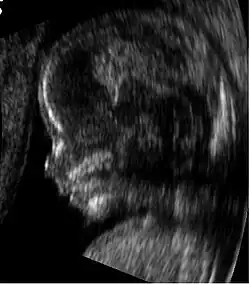

Ultradźwięki znajdują także zastosowanie w medycynie. Za pomocą urządzenia generującego i rejestrującego fale ultradźwiękowe (ultrasonograf) można uzyskać obraz narządów wewnętrznych. Fale dźwiękowe znalazły szerokie zastosowanie np. w stomatologii do tzw. skalingu, tj. ultradźwiękowego usuwania kamienia nazębnego.